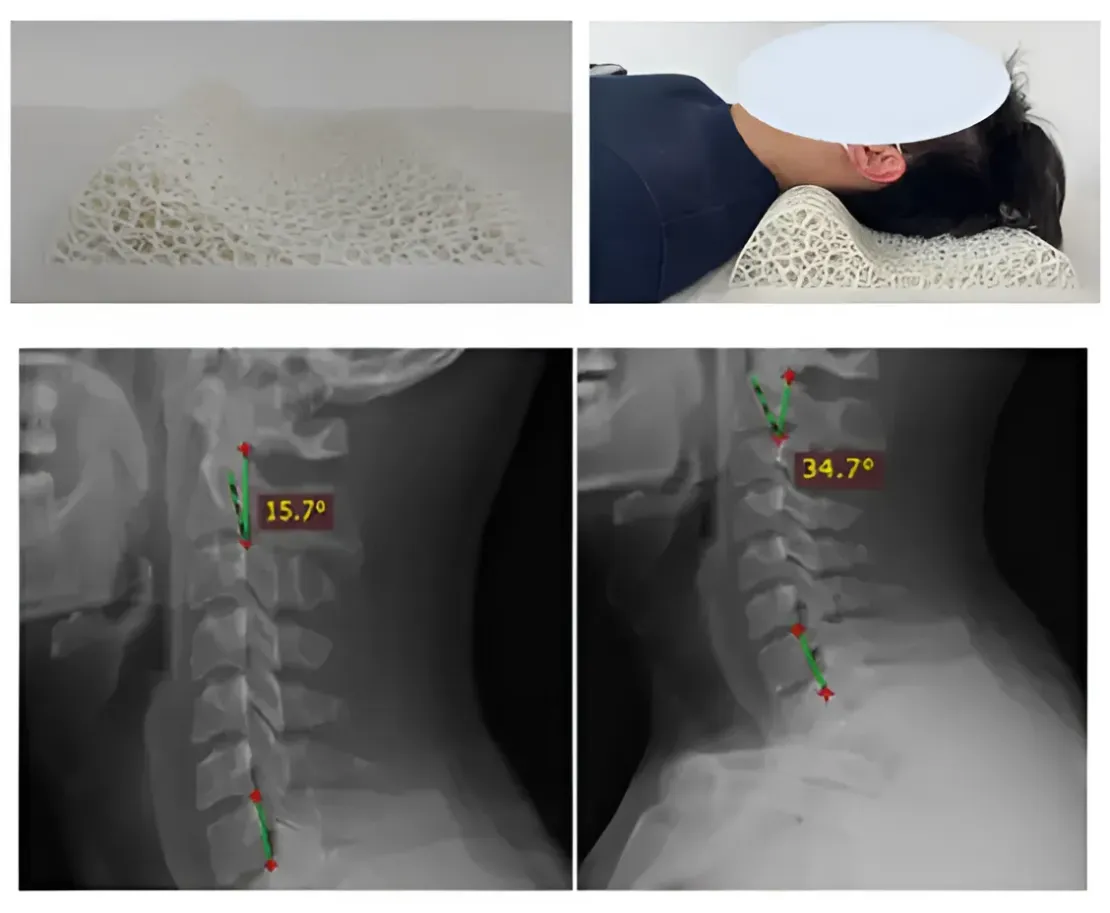

Подголовник из термопластичного полиуретана, изготовленный с помощью 3D-сканирования + рентгеновской съёмки + технологии SLS, идеально подстраивается под изгиб шеи каждого человека. По сравнению с вспененным латексом, термопластичный полиуретан обладает более высокой несущей способностью и меньшей деформацией при давлении. Он также не деформируется при длительном использовании, что позволяет эффективно снимать усталость с шеи и постепенно корректировать изгиб шейного отдела позвоночника.

Влияние ортопедического подголовника TPM SLS 3D-печати на изгиб шеи